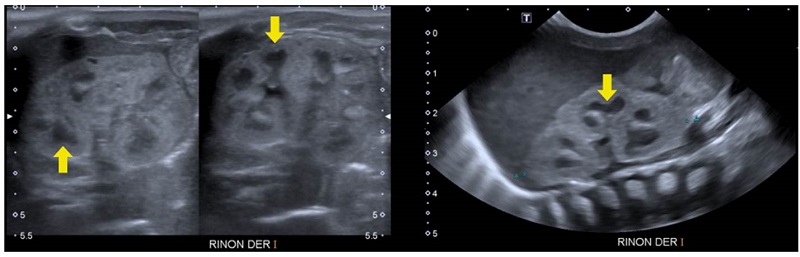

Se trató de un paciente de sexo masculino que a los dos años de vida presentó un cuadro clínico de lesión renal aguda KDIGO 3 en el contexto de una infección gastrointestinal 9. Se practicó una ecografía renal que evidenció la dilatación de las vías urinarias del lado derecho, por obstrucción secundaria a estenosis de la unión pieloureteral, con un riñón izquierdo de apariencia displásica multiquística (figura 1).

Análisis. Los riñones displásicos multiquísticos son masas renales no funcionales, causados por alteraciones en la diferenciación metanéfrica y caracterizados por la presencia de múltiples quistes que reemplazan en su totalidad el parénquima renal. Usualmente, se visualizan en la evaluación ecográfica prenatal; hay afectación de un solo riñón y tienden a involucionar en el útero o después del nacimiento en el 95 % de los casos. Esta condición suele ocurrir de manera esporádica; sin embargo, se han visto casos donde hay agregación familiar o puede presentarse en el contexto de condiciones multisistémicas por mutaciones en los genes EYA1, SIX1, HNF1B y PAX2, entre otros 10.